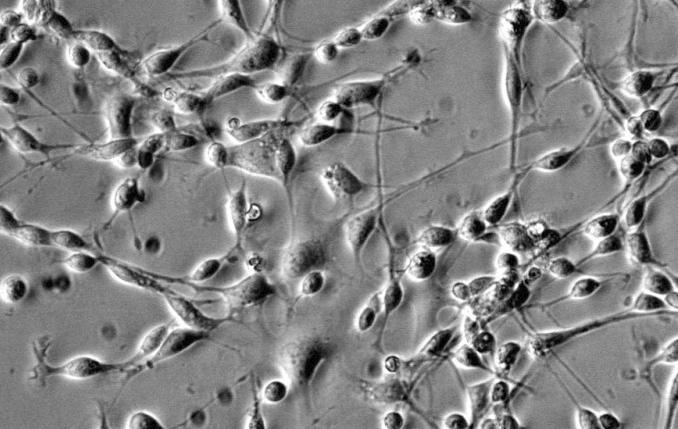

UM-UC-3,人膀胱移行细胞癌

UM-UC-3人膀胱移行细胞癌|UM-UC-3细胞|人膀胱移行细胞癌|UM-UC-3细胞|人膀胱移行细胞癌|UM-UC-3

UM-UC-3 (人膀胱移行细胞癌)

【UM-UC-3细胞】|UM-UC-3【人膀胱移行细胞癌】UM-UC-3

UM-UC-3 / UM-UC-3细胞 / UM-UC-3人膀胱移行细胞癌

UM-UC-3(人膀胱移行细胞癌)

UM-UC-3 人膀胱移行细胞癌

人膀胱移行细胞癌,UM-UC-3

UM-UC-3人膀胱移行细胞癌

人膀胱移行细胞癌;UM-UC-3

人膀胱移行细胞癌(UM-UC-3)

人膀胱移行细胞癌UM-UC-3

人膀胱移行细胞癌.UM-UC-3

UM-UC-3细胞|人膀胱移行细胞癌| UM-UC-3细胞

人膀胱移行细胞癌,UM-UC-3细胞

UM-UC-3 膀胱移行细胞癌